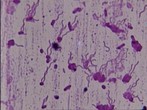

淋球菌鉴定

初步鉴定:菌落特征、氧化酶试验和革兰染色是初步鉴定淋球菌的三个主要依据。菌落:选择性培养基上分离出的淋球菌菌落大小及形态随培养基及培养时间的不同可有差异。一般而言,在巧克力培养基平皿上生长24h时直径大约…